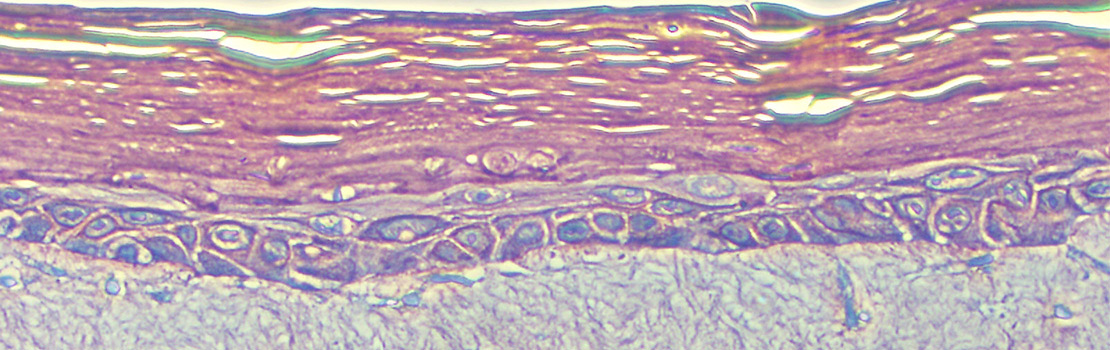

核重编程的第一步是核转移简言之,这意味着体细胞内含脱氧核插入已经去除核的鸡蛋细胞体细胞核再编程宿主鸡蛋细胞,并经过多单元分周期后,将形成先阶段胚胎,DNA与原生生物完全相同,供体体核取自原生生物

头系统Miyamoto博士调查鼠标体核核转入鼠标细胞细胞必须处于开发阶段 即元阶段二 准备受精重新编程越来越不成功,宿主单元开发阶段推延并提出了另一个问题:在胚胎开发过程的哪个点上,oocytes/embryos重编程序能力会丢失?

过程产生原鼠标克隆子尽管初步成功,动物克隆率很低,表明其他因素正在起作用。深入调查显示,这一低成功率是由于体细胞编程不全,特别是异常子元重编程单片专用函数时,如神经或肺细胞,自有模式,称为后代特征,保持自有状态然而,即使在核转至子元后,这种子元签名仍可持久化,防止克隆子子开发

另一种鼓励体细胞实现这些变换的可能系统是将哺乳动物体核移植成青蛙卵细胞,具体地说,移植成细胞中被称为子宫的一部分青蛙细胞的这个区域以包含重新编程因子而闻名20世纪50年代John Gurdon教授成功使用体格青蛙细胞实现克隆Miyamoto博士和Gurdon实验成员曾使用此系统探索重新编程机制并识别核编程负责基因之后这些基因有可能用于其他系统重编细胞,例如再生医学,该医学旨在开发方法重造、修复或替换病人受损器官或组织